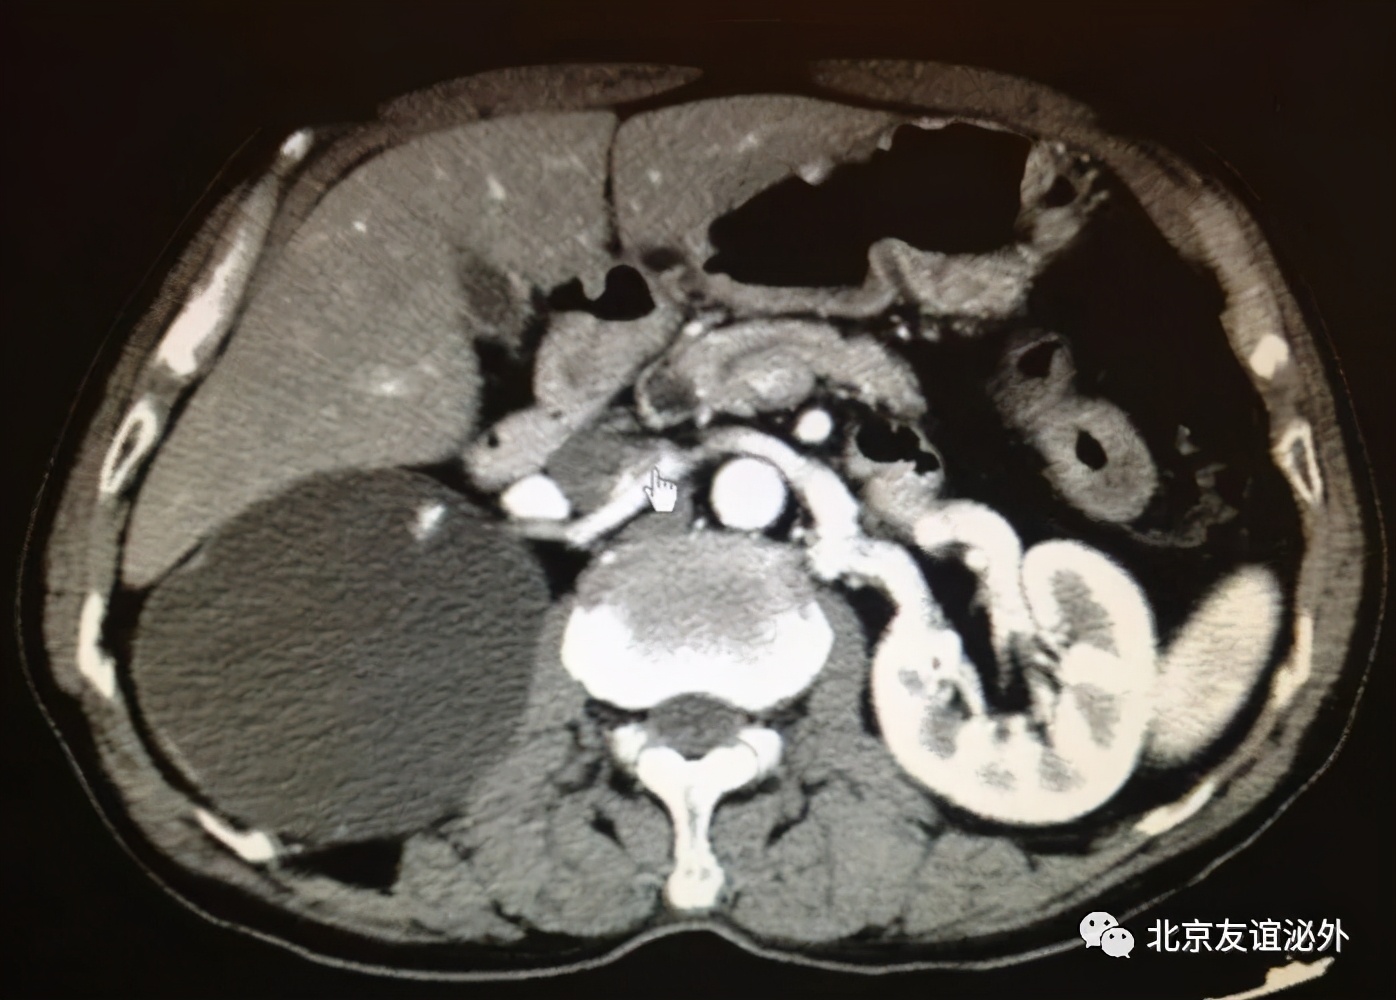

图3. Bosniak II级良性囊肿(囊肿内少量细小分隔)